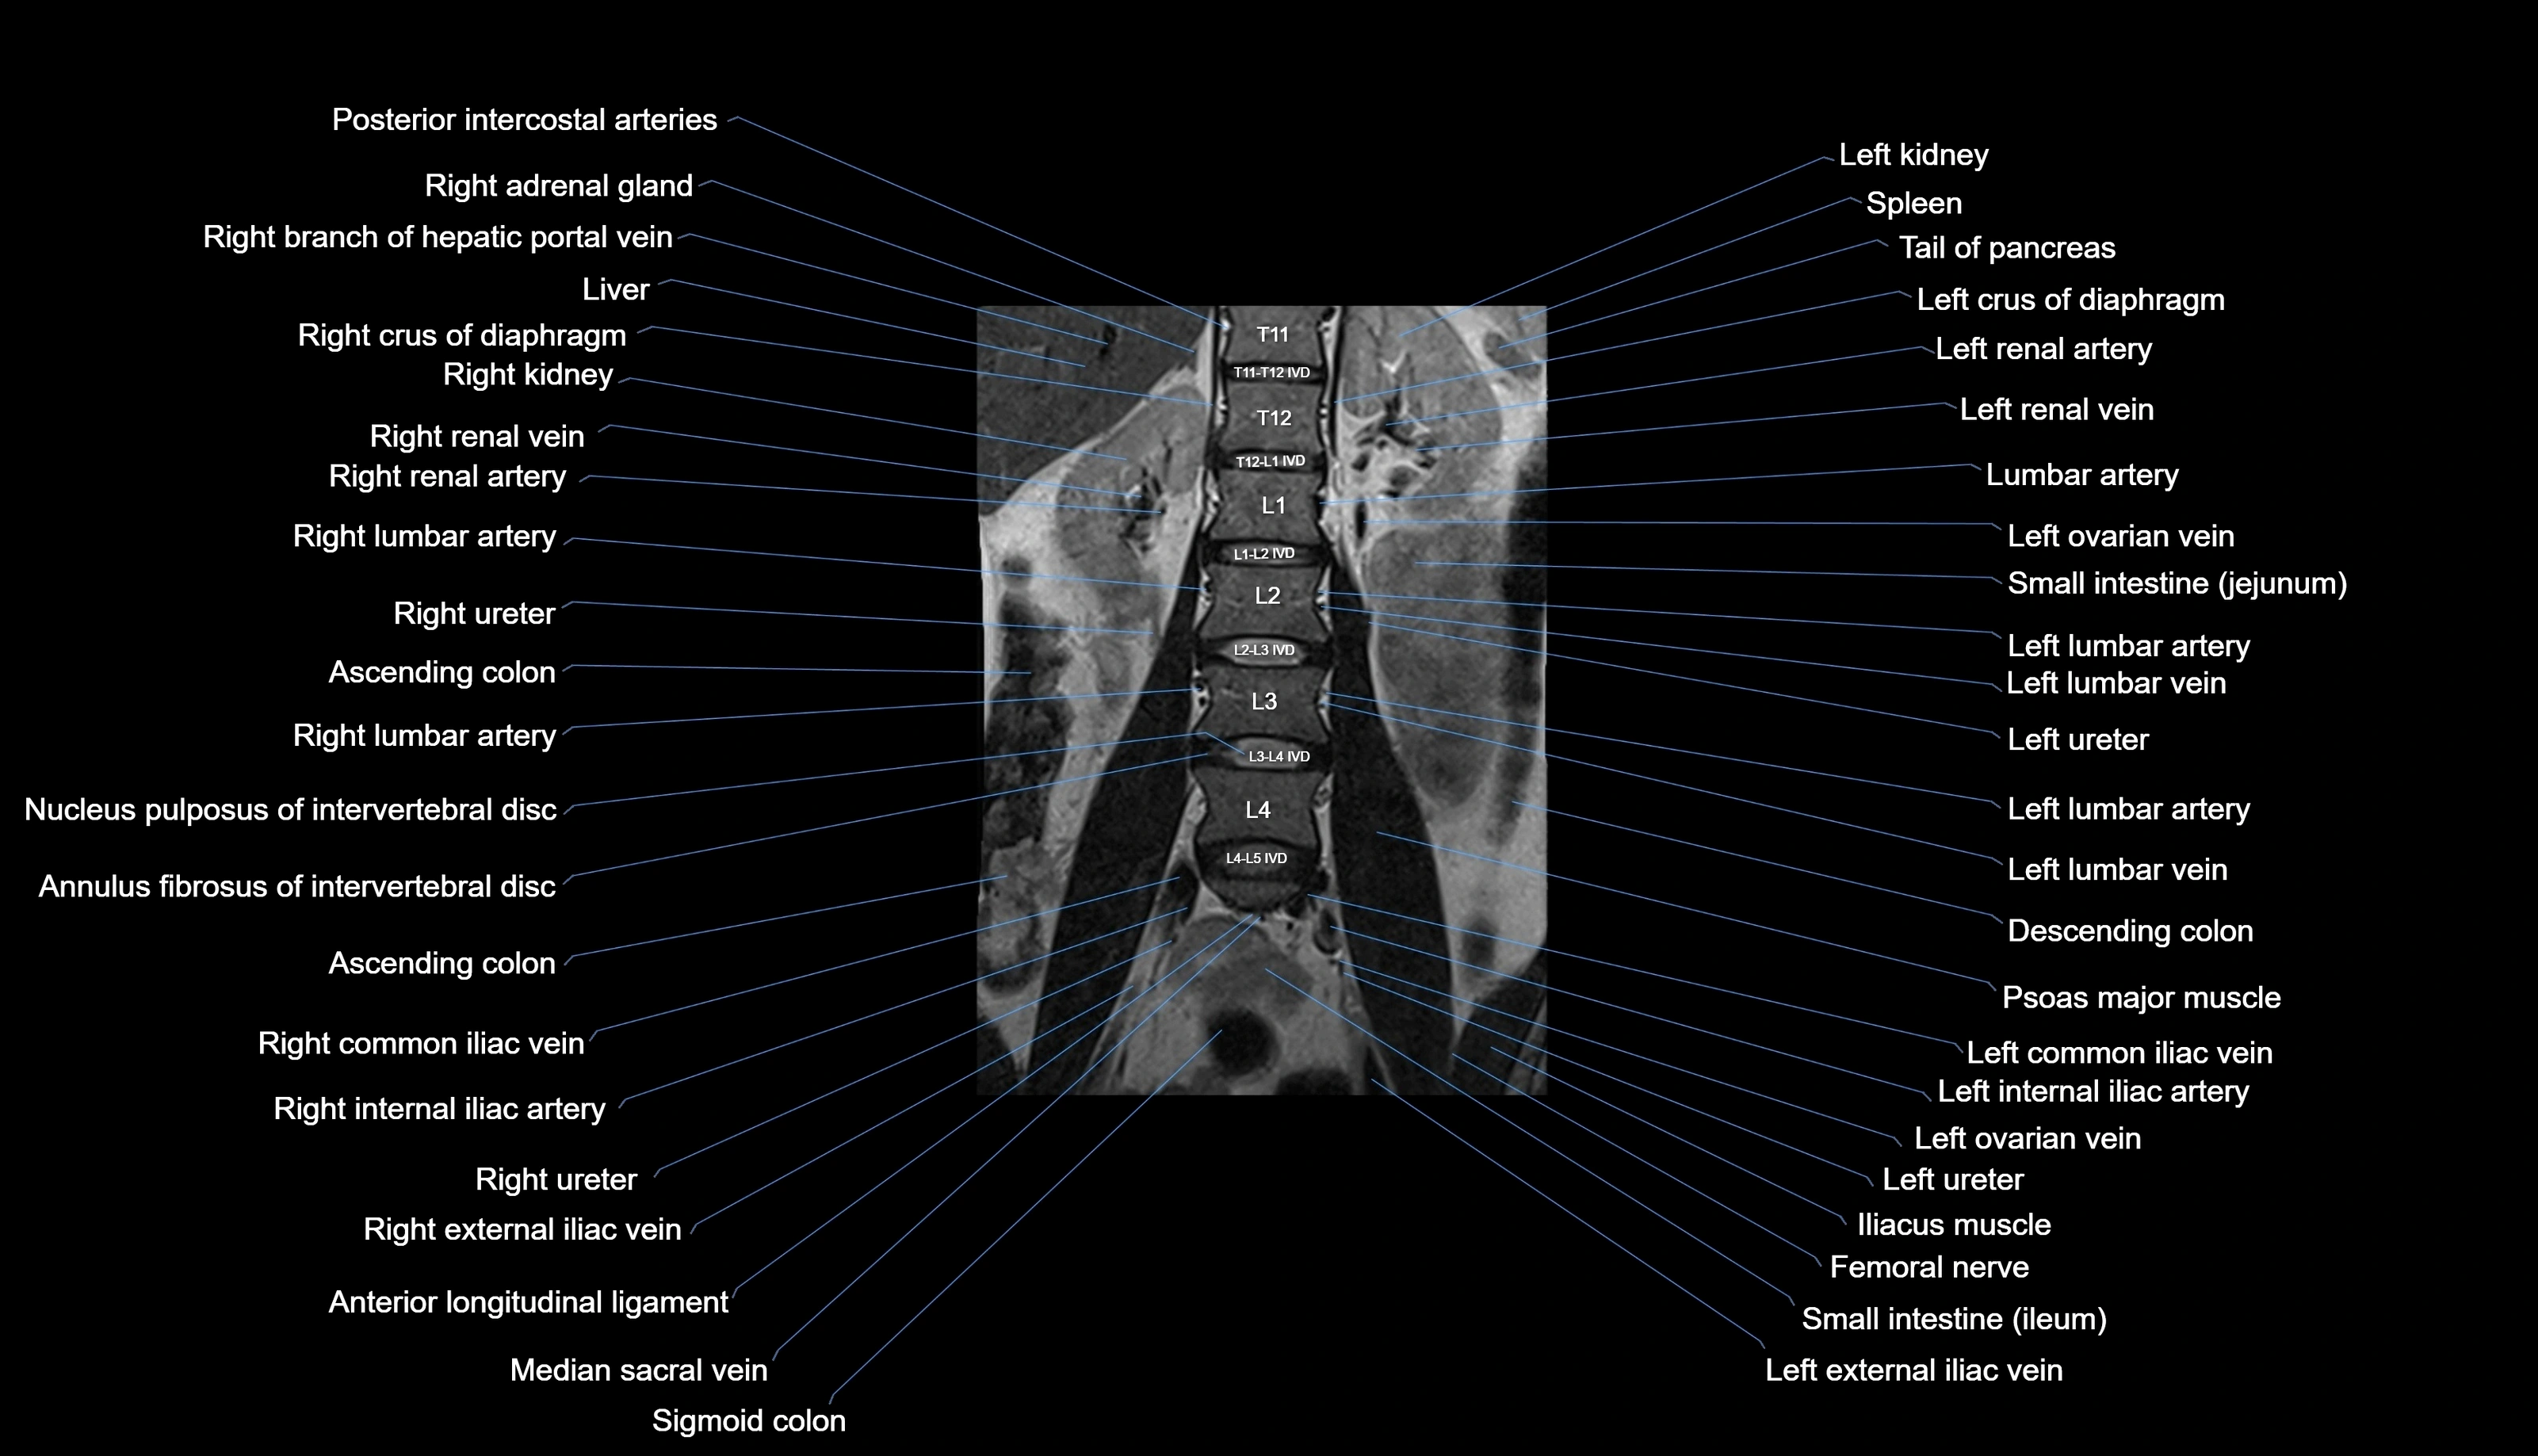

MRI images